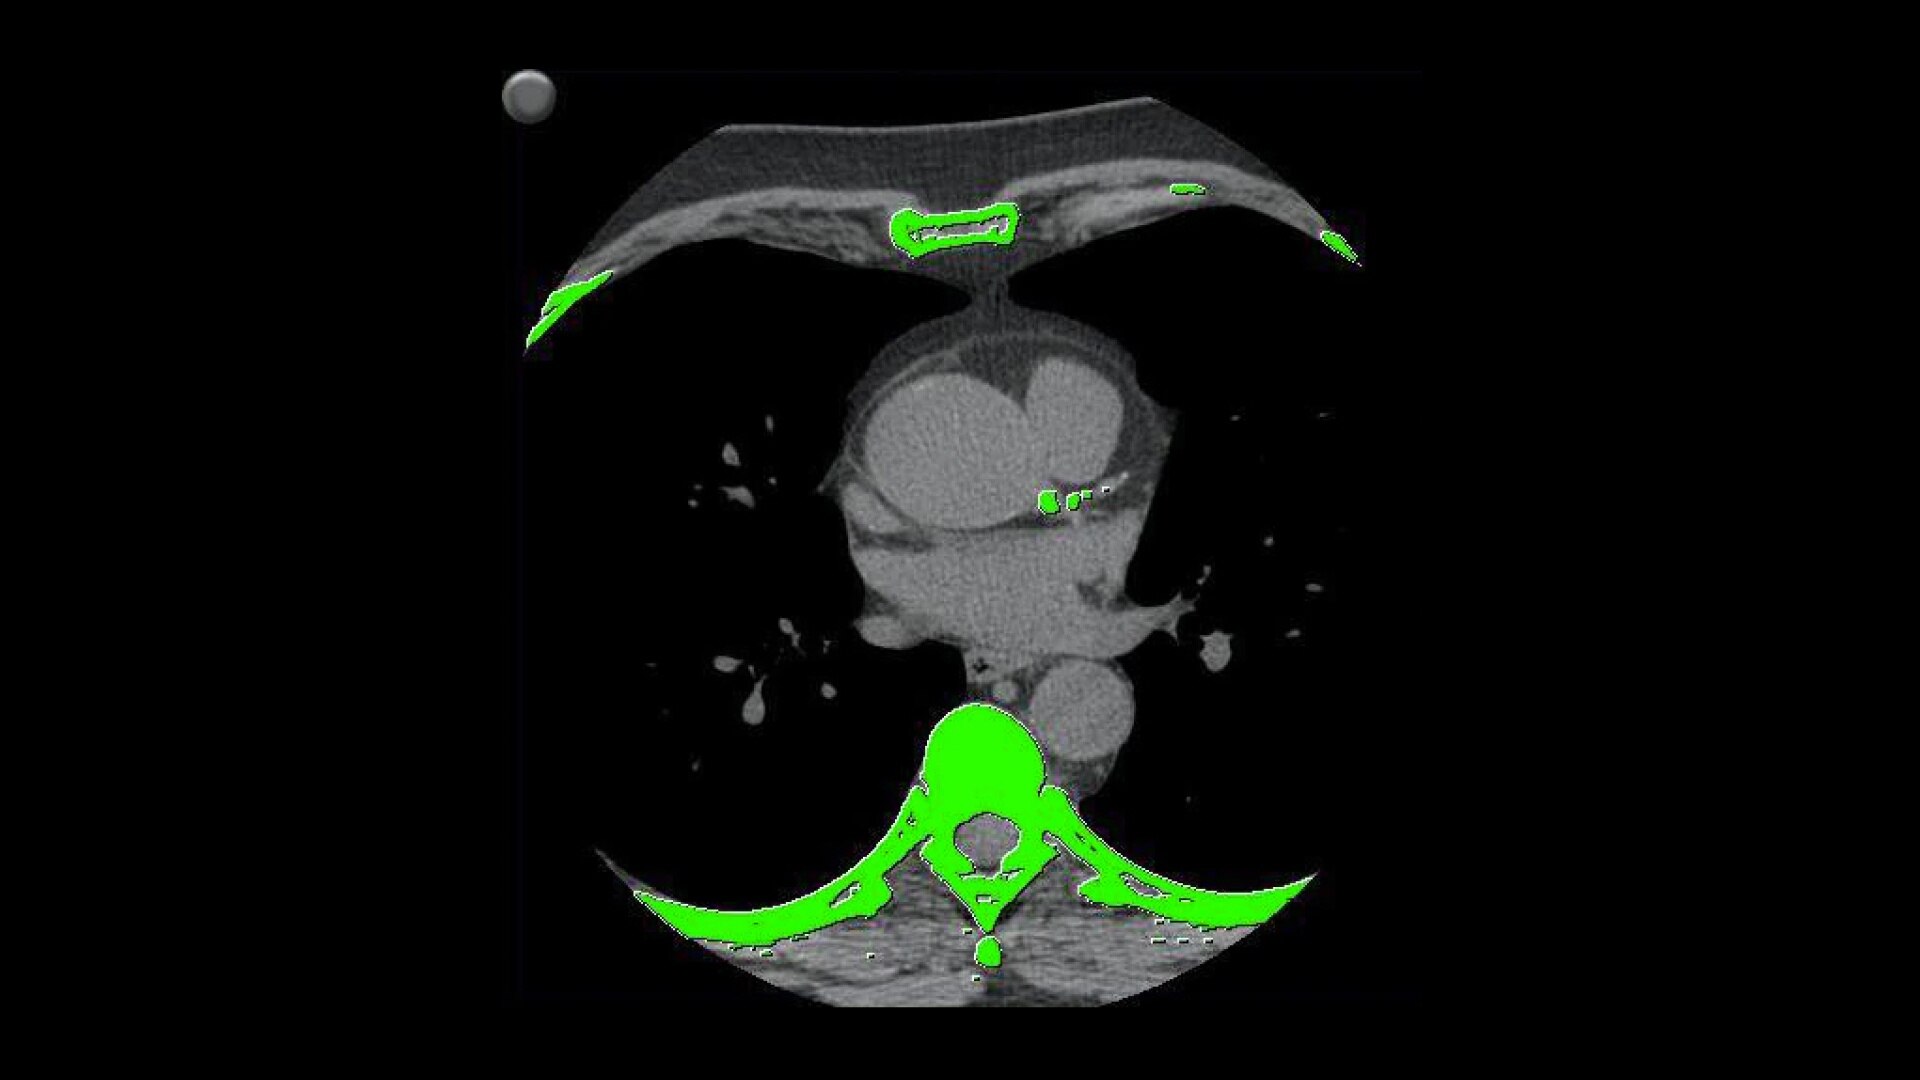

• Automatically detects calcium and highlights it in green